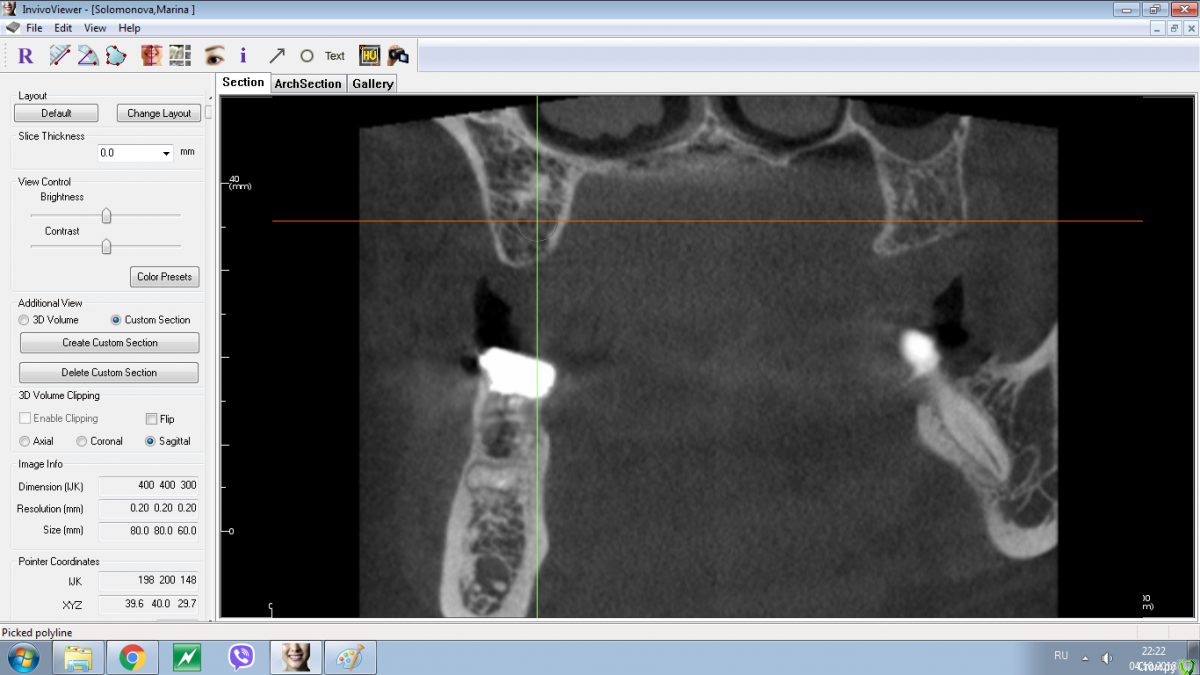

Nazim_NV86 Опубликовано 4 октября, 2018 Поделиться Опубликовано 4 октября, 2018 А как Вы проверяете интеграцию?На ощупь и на глаз )) Если заглушка покрыта хоть немного костью, этого факта достаточно. Если при выкручивании её прилагаются усилия. Ключ никогда не использую. По поводу подождать или перекрутить не могу однозначно сказать. КТ бы. Я бы не стал спустя 4 месяца ещё надеятся раз вы говорите что ставили не в графт. Ссылка на комментарий

Nazim_NV86 Опубликовано 4 октября, 2018 Поделиться Опубликовано 4 октября, 2018 Проверяйте кость на наличие остатков пломбировочных материалов или другой ятрогении. Ссылка на комментарий

Nazim_NV86 Опубликовано 4 октября, 2018 Поделиться Опубликовано 4 октября, 2018 А что в области 1.7 ?? Это губка... альвожиль ?? Ссылка на комментарий

Shakirbura Опубликовано 4 октября, 2018 Автор Поделиться Опубликовано 4 октября, 2018 А что в области 1.7 ?? Это губка... альвожиль ??Альвостаз. Ссылка на комментарий

Shakirbura Опубликовано 4 октября, 2018 Автор Поделиться Опубликовано 4 октября, 2018 (изменено) Срез КТ до операции.Здесь наверное можно придраться, не? Изменено 4 октября, 2018 пользователем Shakirbura Ссылка на комментарий